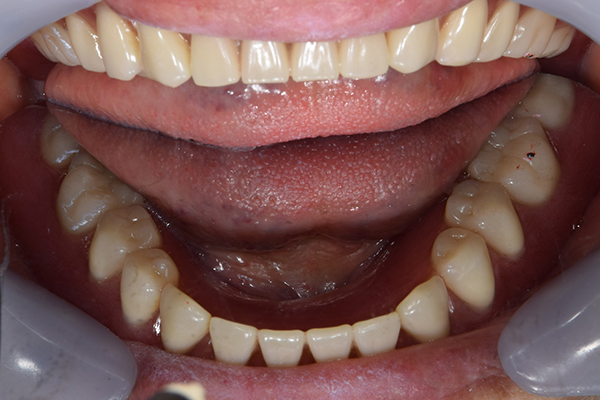

入れ歯をお口の中にいれた状態です。前歯もMTMといって、歯を少し引っ張り出す処置を行なったことで、しっかり残せて、またかぶせ物をしました。

お口の中に入れた状態です。 見た目も最初とほとんど変わることなく作成できました。 維持や吸着に関しても問題ないようでした。

入れ歯を入れた状態のお口の中の写真です。バネも極力目立たないように作成しています。

お口の中に入れた状態です。 非常に見た目もよい出来となりました。 バネがみえないと見栄えが全然ちがいます。